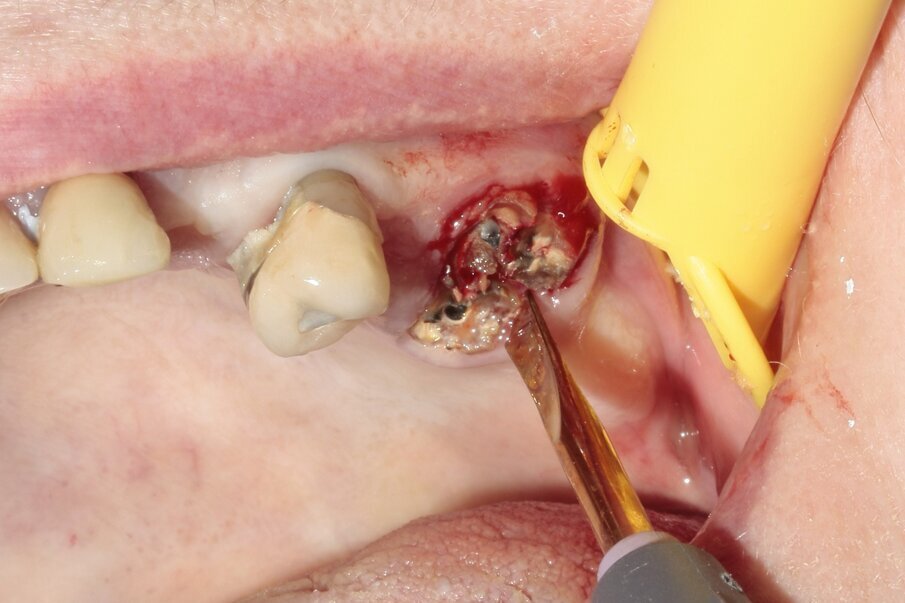

Fig. 3: The tooth was luxated with Luxator P4 (dual edge, lilac).

The new, very thin Luxator P-series periotome made it possible to perform an atraumatic extraction with minimal loss of bone. Luxator P4, with its extremely sharp dual-edge blade, was used, followed by Luxator P1, once some space was created. Although the blades of these sophisticated instruments are reinforced with a titanium coating, they should only be used to cut the periodontal ligament and never to elevate the tooth. After sectioning the tooth and gently cutting the periodontal ligament, each root could easily be taken out with the help of diamond tweezers.